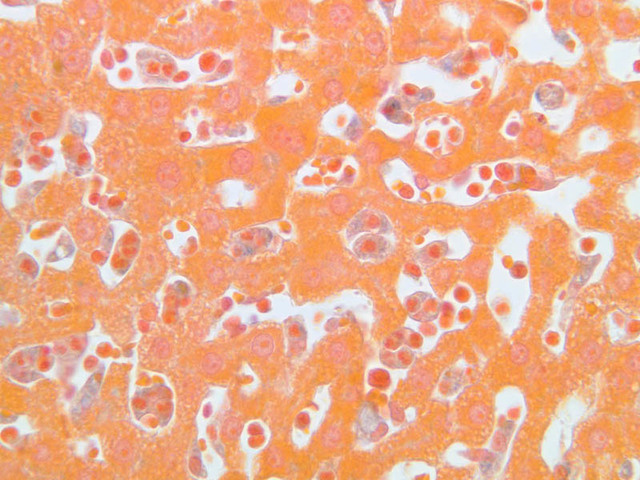

The specimen on slide B-39 was prepared by perfusing India ink into the blood stream of an animal. Examine this specimen with an eye to understanding how the capillary beds of the exocrine and endocrine portions of the pancreas differ (B-39, Ink/H&E [10x, 20x-labeled] [10x] [10x, 20x]).

9 Islet of Langerhans IL, (circled area) H&E, Ink/H&E b36 interlobular duct pancreas 10x labeled.jpgB36, Pancreas, 10x; b36 islets of langerhans pancreas 40x labeled.jpgB36, Pancreas, 40x; b39 capillary beds pancreas 20x ink he labeled.jpgB39, Pancreas, 20x

11 Capillary (none) Ink/H&E b39 capillary beds pancreas 20x ink he labeled.jpgB39, Pancreas, 20x